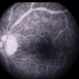

- Behcet's Disease, Behcet's uveitis, FA late phase leakage

- A 19-year-old boy presented with with recurrent oral and genital ulcers along with blurring of vision. Systemically he was HLA B-51 Positive suggesting Behcet's Disease. The FFA photograph depicts the classic small vessel immune mediated vasculitis predominantly affecting the capillaries (capillaropathy).